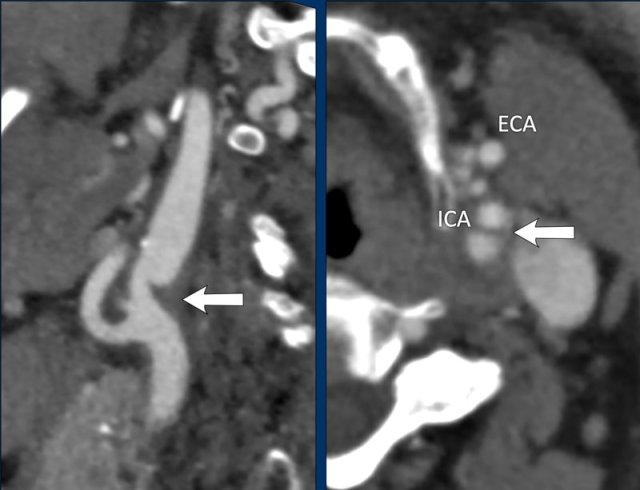

On the saggital view there is a longitudinal filling defect

in the proximal internal carotid artery (arrowheads).

This filling defect is a

floating thrombus attached to a atherosclerotic plaque located at the carotid

bulb (white arrow).

In the axial plane this floatig thrombus causes a central filling defect in the ICA also now as a “donut sign” (arrowhead).

In case of an

accompanying intracranial occlusion of a large vessel endovascular therapy is

initiated to open this intracranial occlusion.

An isolated floating thrombus

(no large vessel occlusion) is treated with heparine or

anti-platelet therapy .